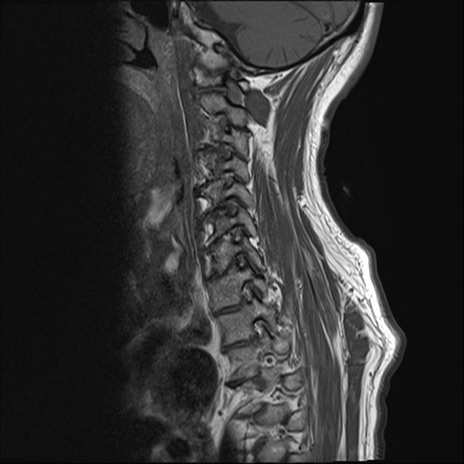

【整形】TIPS症例7 頚椎MRI T1WI(矢状断像)

頚椎MRI

T2WI(矢状断像)

矢状断像と横断像